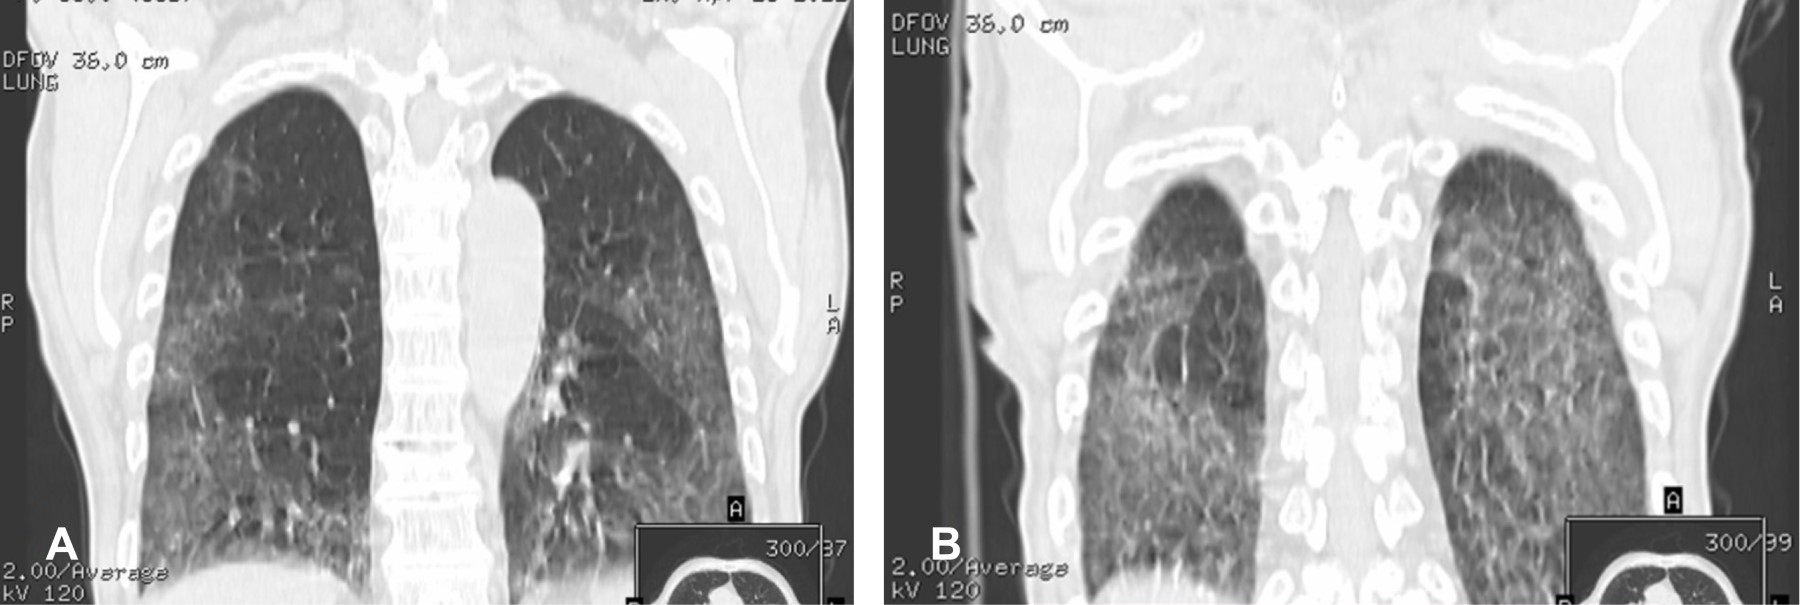

Hombre de 76 años. Inicia hace ocho meses con: debilidad creciente en paravertebrales cervicales y músculos de cintura escapular y pélvica, pérdida de 12 kg, cuenta con endoscopia de tubo digestivo alto y bajo normales y tomografía computarizada (TC) de tórax, mostrando neumopatía intersticial (Figura 1). A la exploración: tensión arterial 110/60 mmHg; frecuencia cardiaca 84/min; frecuencia respiratoria 24/min; temperatura 36.6 oC; peso 60 kg; talla 177 cm; índice de masa corporal 19.2. Oximetría de 90. Postura: columna cervical en flexión con barbilla pegada al tórax y cifosis dorsal; marcha asistida con aumento en base de sustentación; cuello en flexión con barbilla en pecho (Figura 2), paravertebrales cervicales en 1/5. Extremidades: calificación 3/5 para músculos de cintura escapular y pélvica, resto en 5/5.

Figura 1